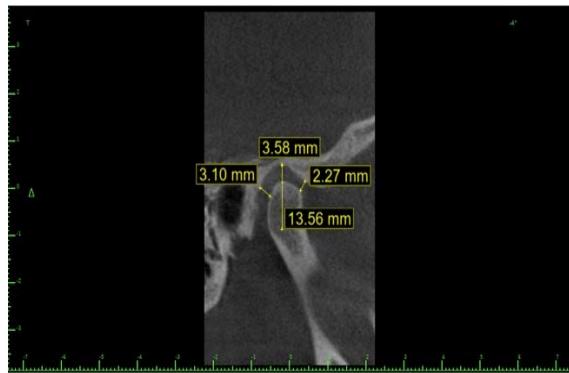

The right and left sides were analyzed separately. The sagittal measurements (MS) evaluated were (FIGURE 1):

1. Depth of the articular fossa: measured from the uppermost point to the horizontal plane with the lowermost point of the external acoustic meatus.

2. Anterior articular space: determined by the shortest distance between the condyle's most anterior point and the articular tubercle's posterior wall.

3. Superior articular space: measured by the shortest distance between the condyle's uppermost point and the articular fossa's uppermost point.

4. Posterior articular space: determined by the shortest distance between the condyle's most posterior point and the articular fossa's posterior wall.

Figure 1: Illustration of the measurements in the sagittal section

Figure 3: Sagittal section measurements